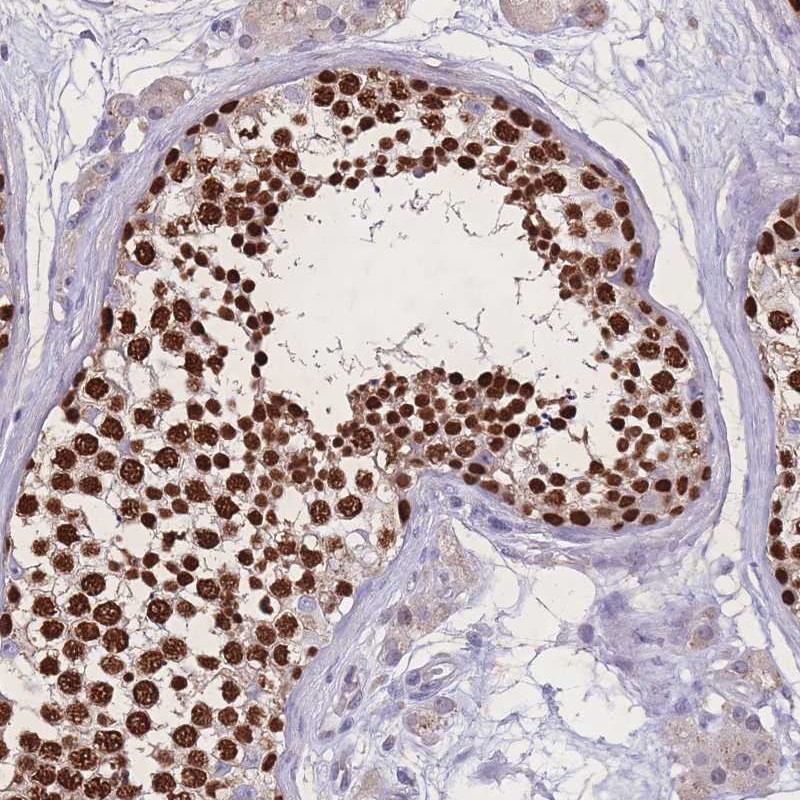

Immunohistochemical staining of human testis shows strong nuclear positivity in cells in seminiferus ducts.